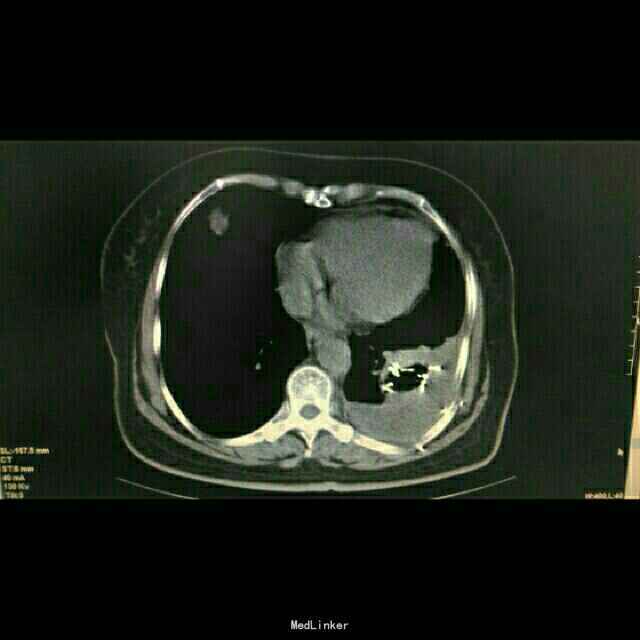

查体:体温:36℃,脉搏:86次/分,呼吸:21次/分,血压:137/81mmHg,胸廓无畸形,两侧对称,双肺呼吸动度一致,左下肺呼吸音减弱,未闻及干湿罗音。心率:86次/分,律齐,心前区及各瓣膜听诊区未闻及杂音,腹软,无压痛及反跳痛。双下肢体无水肿。 辅助检查:胸部CT示:左肺下叶,双肺多发转移灶。于10月16日行左侧胸腔积液穿刺引流,胸水病理检查示:可见少许核异型细胞,考虑为腺癌细胞 颅脑MR检查示:右侧小脑半球两处异常信号,转移瘤可能,右侧放射冠区陈旧性腔梗。

中医诊断: 肺积 正虚瘀结 西医诊断: 1.左肺占位性病变:双肺转移? 2.2型糖尿病 3.冠状动脉粥样硬化性心脏病 治疗经过:,于10月8日下午行左肺占位穿刺活检,病理回报示:不除外细支气管肺泡癌。于10月12日下午行左肺癌碘125粒源植入术,围手术期给予抗感染、支持治疗。于10月16日行左侧胸腔积液穿刺引流,胸水病理检查示:可见少许核异型细胞,考虑为腺癌细胞,给予胸腔药物灌注治疗。于10月25日-29日给予患者生物细胞免疫DC+CIK治疗。 患者家属拒绝静脉化疗,给予口服特罗凯治疗!

患者治疗后一月余行肺ct检查病灶肺部病灶明显缩小!口服特罗凯治疗耙向治疗!